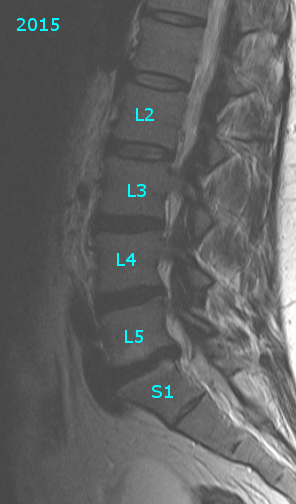

Grade 1 retrolisthesis at l5 s1 image This image demonstrates grade 1 retrolisthesis at l5 s1.

Grade 1 retrolisthesis at l5 s1

Annoyance Management 13 days experience XRay findings: This means that your L5 os body has emotional slightly backwards terminated S1. Grade 1 means it is mild.